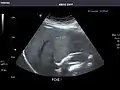

Abdominal Ultrasound (Full Exam)

STRUCTURED REPORT

(Technique: Transabdominal ultrasonography; Device: Toshiba Aplio XG)

Liver: Diffusely homogeneous and normal in echogenicity. No focal mass or contour nodularity. No intrahepatic biliary ductal dilatation.

Portal Vein: Patent main portal vein.

Gallbladder: No stones, wall thickening, or pericholecystic fluid.

Common Bile Duct: Nondilated measuring 1.3 mm at the level of the porta hepatis.

Pancreas: Visualized portions unremarkable.

Spleen: Normal in size.

Kidneys: Right and left kidneys measure 11.5 cm and 12 cm in length respectively. No hydronephrosis. Small left lower pole kidney cyst.

Ascites: None.

Aorta: Visualized portions normal in caliber, 16 x 15 mm.

IVC: Normal.

IMPRESSION:

Normal abdominal ultrasound.